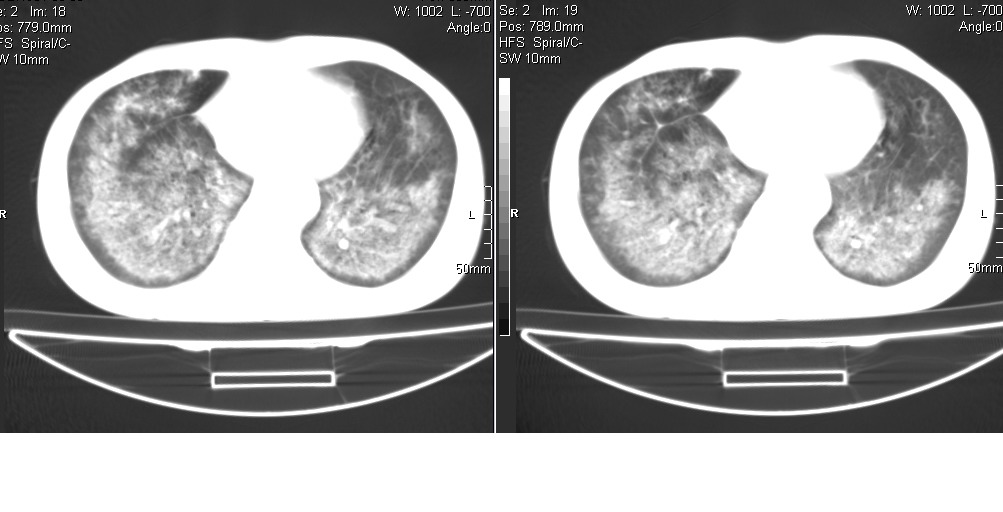

以下是引用光线在2008-5-6 18:36:00的发言:[br]双肺结核(左上肺空洞形成)、间质性改变合并感染,右肺大泡;右侧胸膜增厚。

以下是引用zsl6918在2008-5-7 1:54:00的发言:[br]首先肺泡蛋白质沉着症,其次考虑机遇性感染。